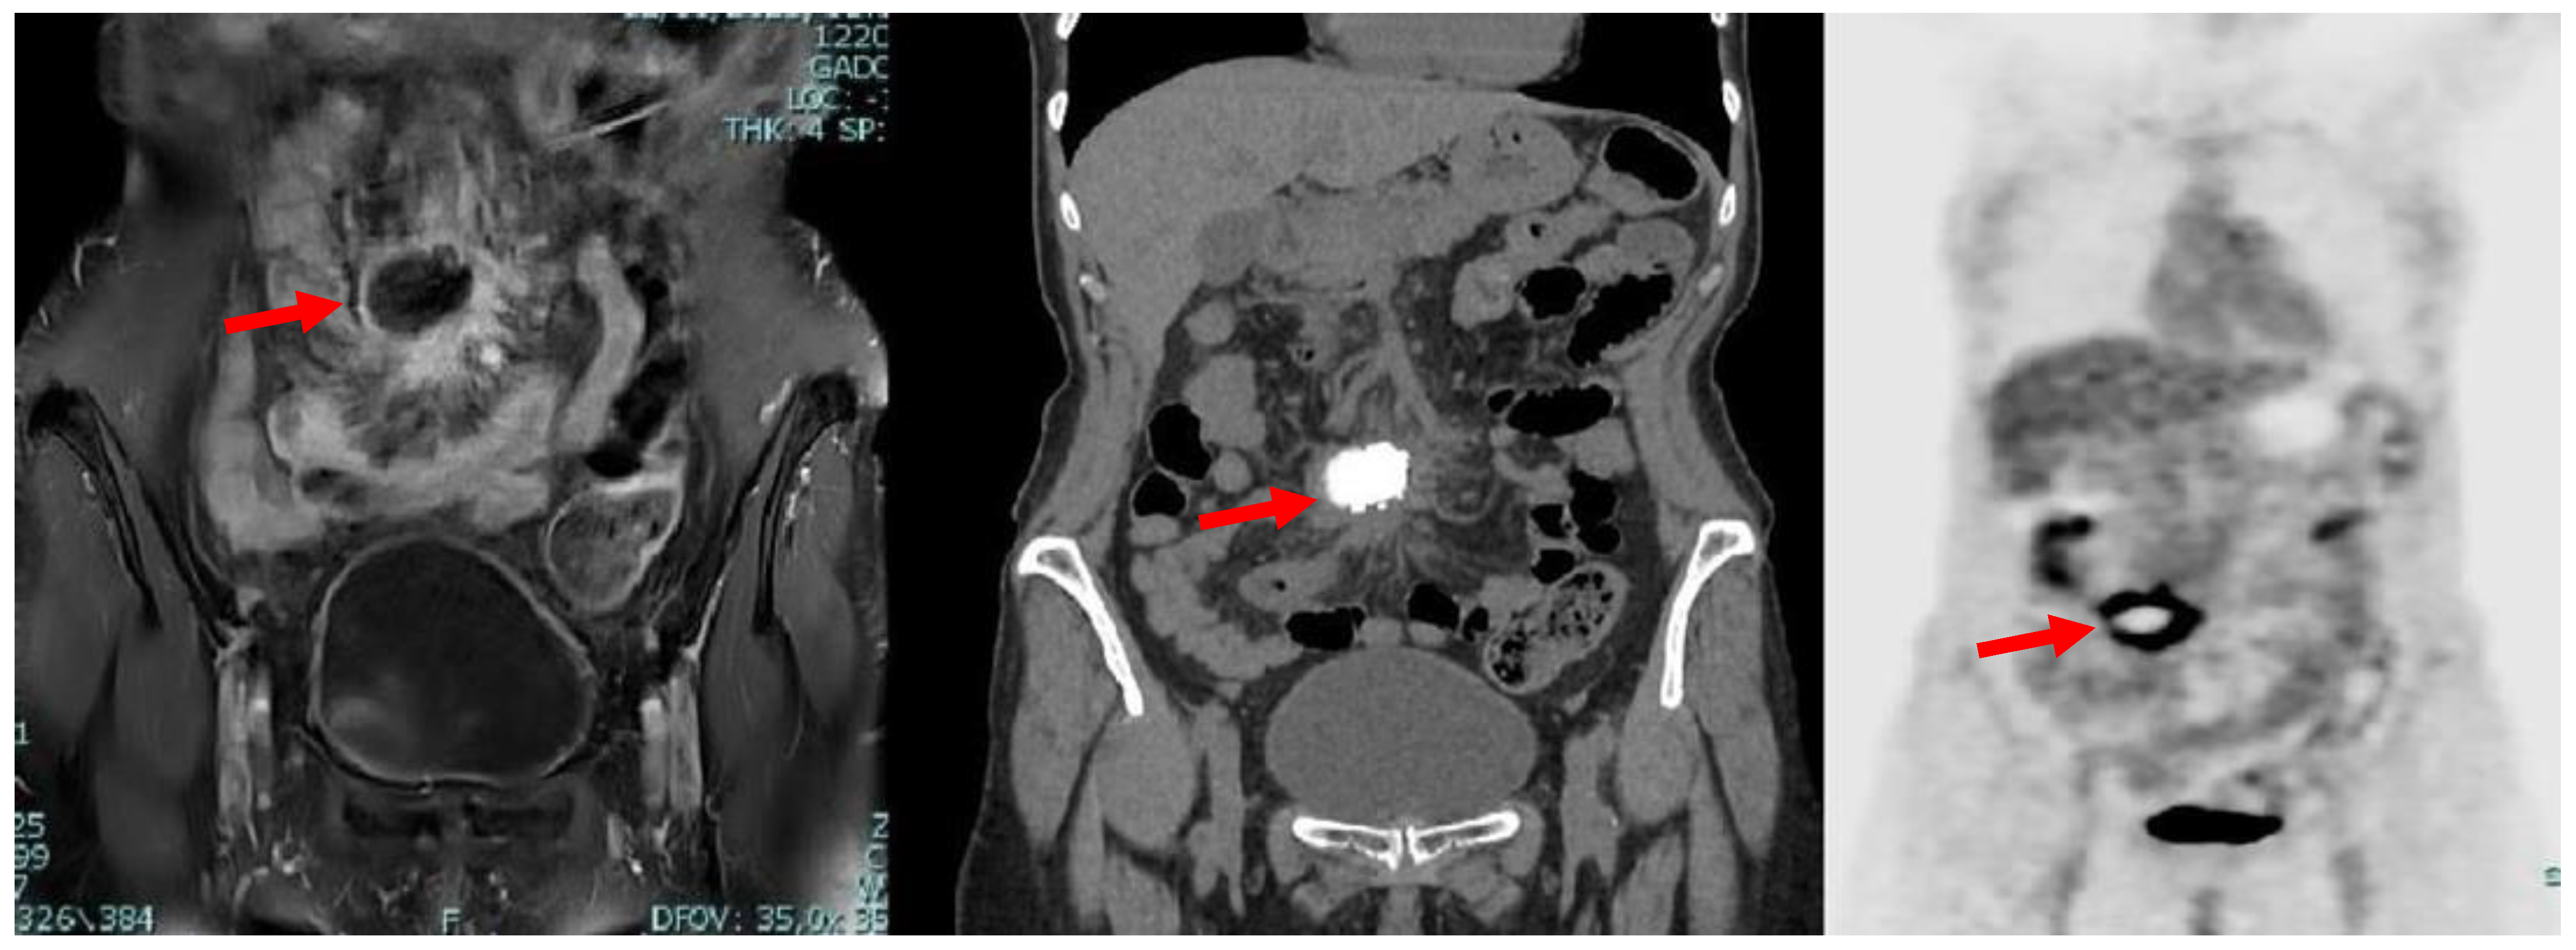

Due to iodinated contrast agent allergy, the patient underwent abdominal contrast-enhanced magnetic resonance imaging (CE-MRI) scan complete with computed tomography (CT) scans documenting, in the hypogastrium, the presence of voluminous multilobular lymphadenopathies (about 45 mm of maximum diameter) with calcific nucleus surrounding the mesenteric vessels and infiltrating the mesenteric fat (Figure 1).

Figure 1.

Axial MRI (left) and CT (right) scan showing the presence, in mesogastrium, of a nodular mass (red arrows) with contrast enhancement at MRI and internal calcifications at CT.

A subsequent positron emission tomography–computed tomography (PET-CT) scan revealed the presence of diffuse and pathological accumulation of the radiotracer (max SUV 13.6) in correspondence with the lymphatic nodules seen in magnetic resonance imaging (MRI) (Figure 2).

Figure 2.

Coronal MRI (left), CT (middle) and PET (right) scans showing the presence, in mesogastrium, of a nodular mass (red arrows) with contrast enhancement at MRI and internal calcifications at CT, with thickened mesenterial fat and significant uptake of the radiotracer at PET-CT.